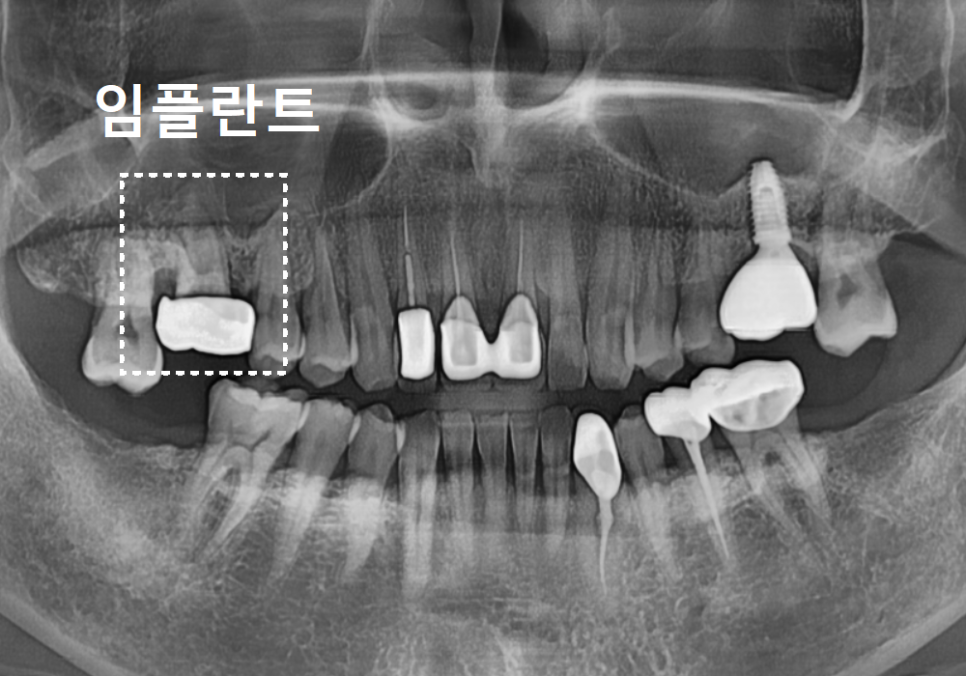

첫 번째 사례, 구멍 난 금니를 가지고 오신 환자분

상일역 치과, 오래된 금니 빠짐

처음 환자분이 오셨을 때는

오른쪽 위 어금니 금니가

빠져서 내원하셨는데요,

240812

가져오신 금니를 받아들고 살펴보니

세월의 흔적이 역력하더군요.

오랜 시간 씹는 힘을 견디느라

금니 표면이 닳아서,

구멍이 '뻥' 뚫려 있는 상태였습니다.

240812 상일역 치과, 오래된 금니 빠짐

입안을 들여다보니

상황은 생각보다 심각했습니다.

금니에 생긴 그 작은 구멍 틈새로

음식물 찌꺼기가 야금야금 들어가면서,

보철물 안쪽의 치아가

아주 심하게 삭아버린 상태였죠.

발치 후 임플란트를 진행하게 되었습니다.

염증으로 녹아내린 잇몸뼈를

단단하게 보강하는

뼈이식을 하고,

임플란트를 식립했습니다.

240831

그리고 뼈와 임플란트가

한 몸처럼 단단히 굳을 때까지

5개월을 묵묵히 기다린 뒤에야,

튼튼한 새 치아를 만들어 드릴 수 있었습니다.

상일역 치과, 오래된 금니 빠짐 241207